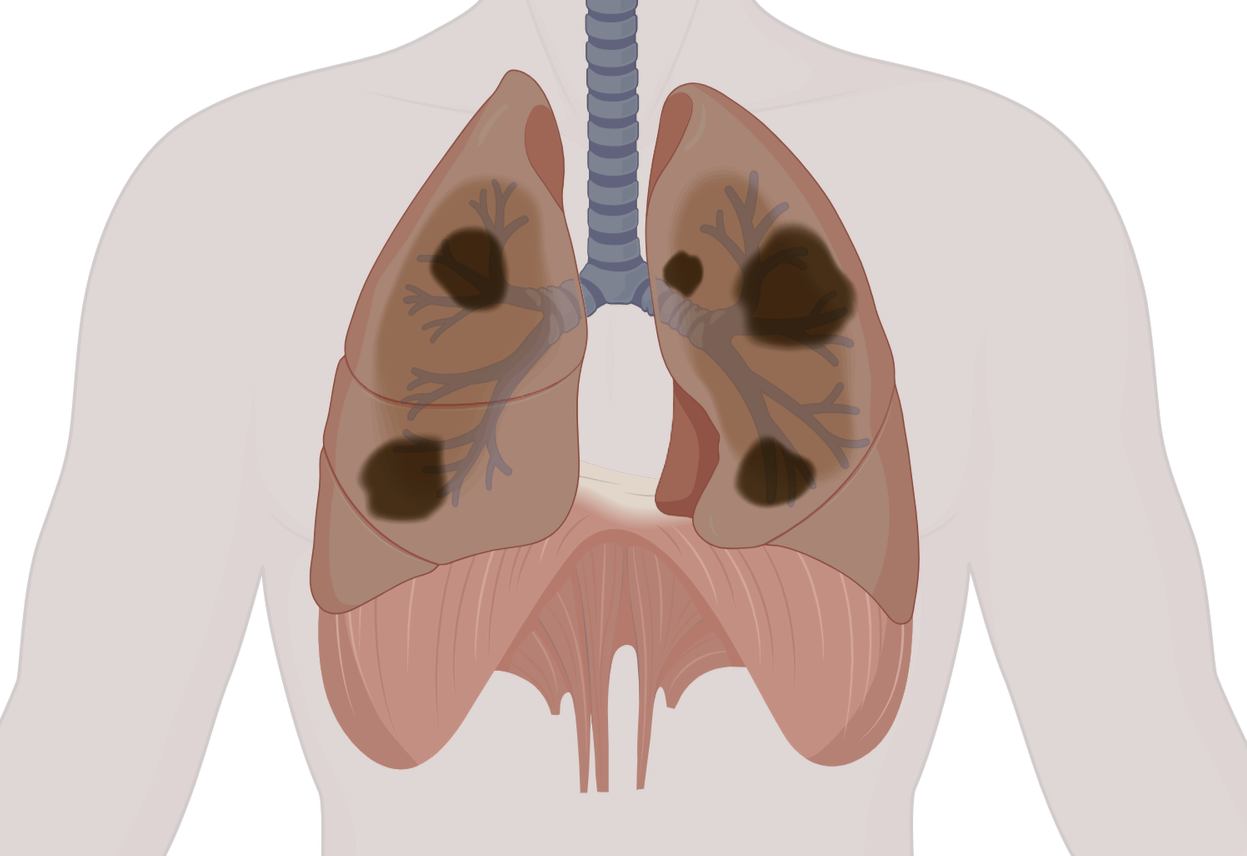

Niveau 2: Pathologie

Formation de 332 heures pour entrer au cœur des mécanismes de la maladie.

Comprendre comment une pathologie naît, évolue, perturbe les équilibres physiologiques… et apprendre à construire une réflexion thérapeutique solide, structurée et stratégique.

Programme reconnu par l’ASCA (cycle 3) et la RME.